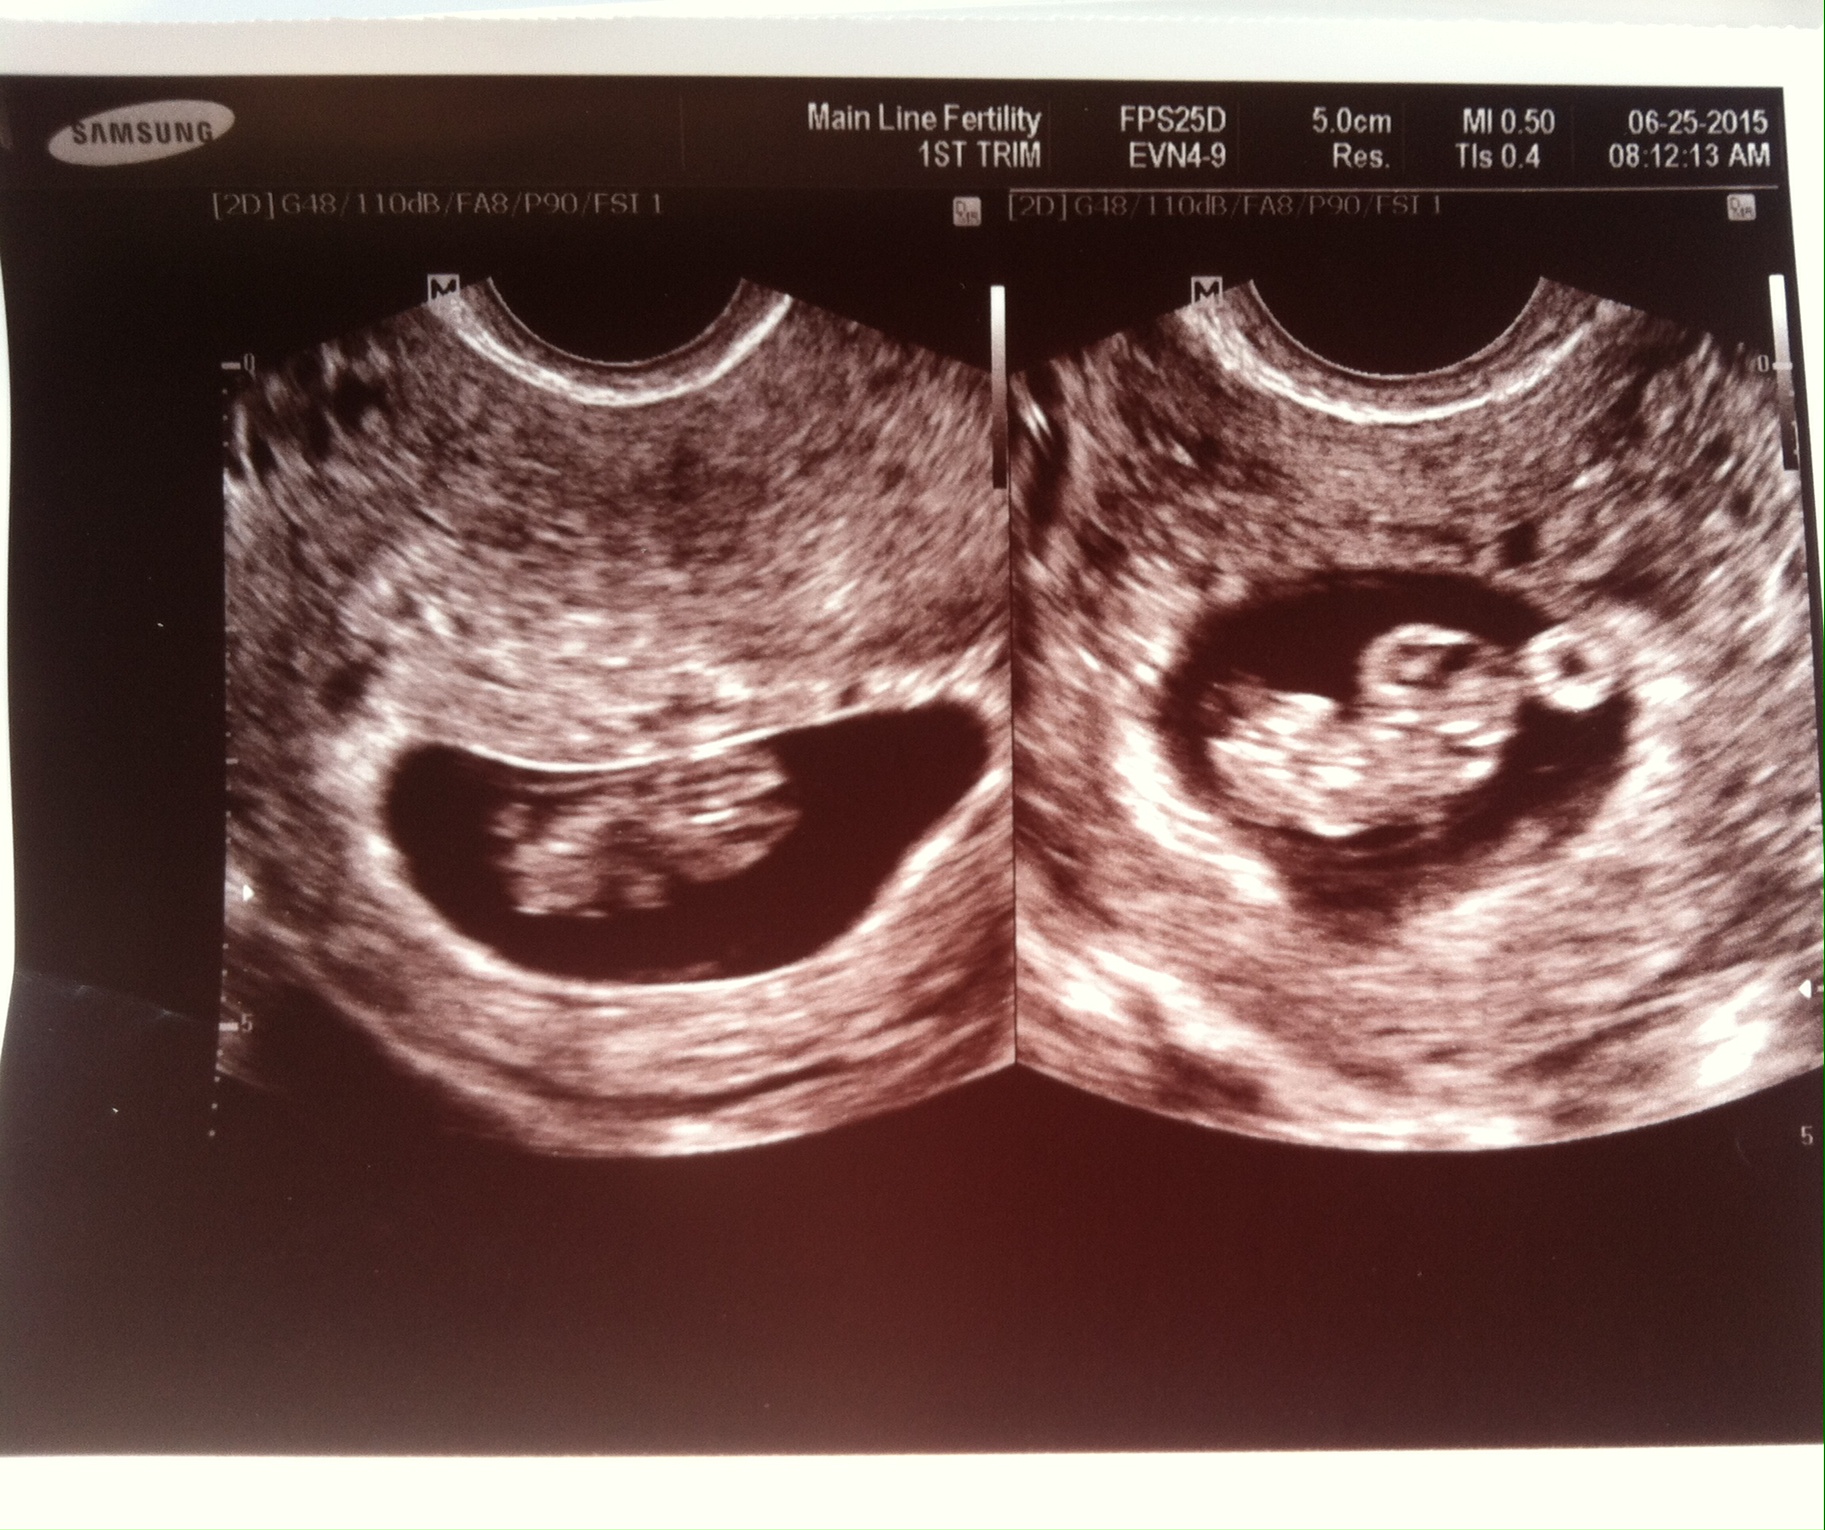

8w5d transvaginal.